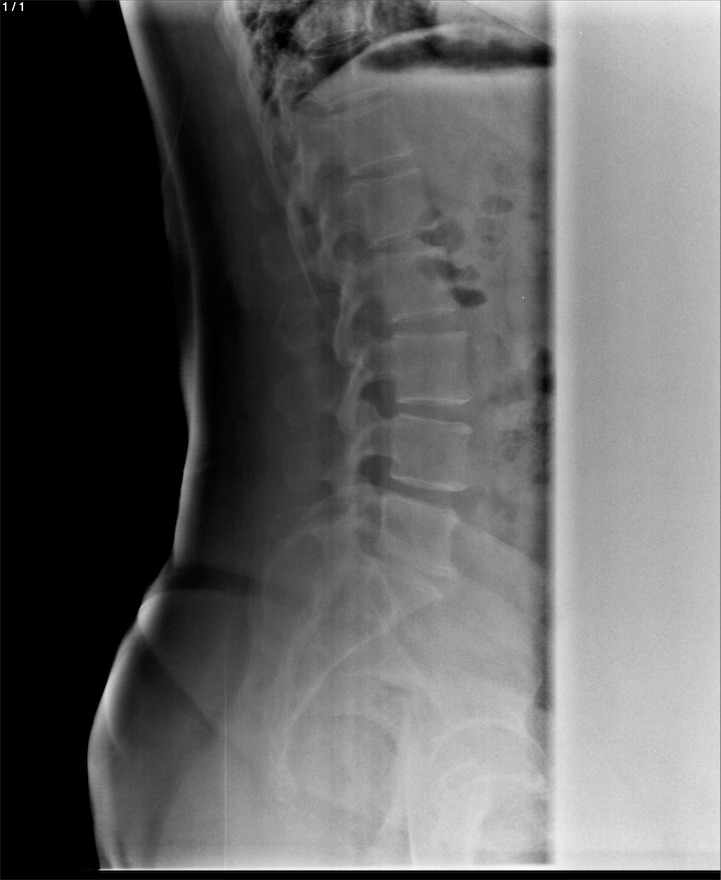

Adulfa Gomez Hernandez - Unnamed